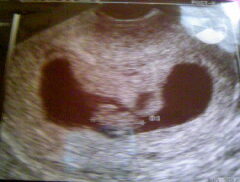

左は前回流産時の子宮内の胎嚢画像。 施術しながら体外受精で妊娠し、右は、出産時の10週時の子宮内の胎嚢画像。

無事に妊娠したものの、出血もあり、不安定で1か月ほど入院していました。 退院後、来院されました。

子宮内の胎嚢の形状が尖っているのと、骨盤のゆるみは5センチ以上ありました。 子宮内の胎嚢の形状が尖っていると流産しやすいという見解を持つ産婦人科医もいます。 ※必ずしも子宮内の胎嚢の形状が丸く改善しないと流産するわけではありません。

そこで、トコちゃんベルト正しい着用を勧めました。 1週間後来院すると、骨盤のゆるみが2センチに改善していました。 無事出産報告がありました。

正しく着用しないと逆に骨盤のゆるみが悪化し、症状の悪化になります。正しく着用して下さい。 |